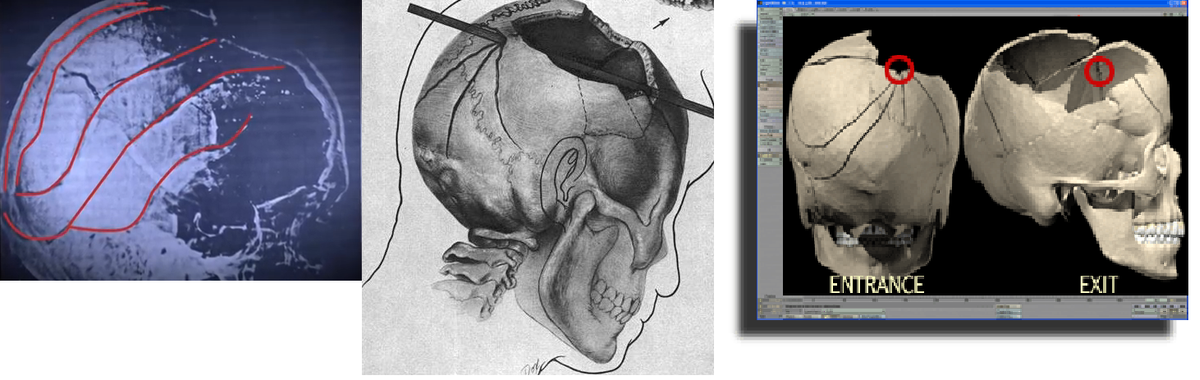

Massensuggestion. Weiter spricht für den Schuss von vorne (aus Richtung des Grashügels), dass dort stehende Passanten einen Schuss/mehrere Schüsse gehört haben (wollen). Dass sich so viele Menschen in genau diesem Moment geirrt haben sollen (aufgrund von Echos, Falschwahrnehmung, etc.) glaube ich einfach nicht.

BTW: Halte ich Dr. Cyril Wecht, der Kennedy u.A. auch autopsiert hat, für einen äußerst fähigen Menschen. Seine Aussagen, die die These des Schusses von vorn ebenfalls stützen, halte ich für

wissenschaftlich korrekt und verständlich wiedergegeben.